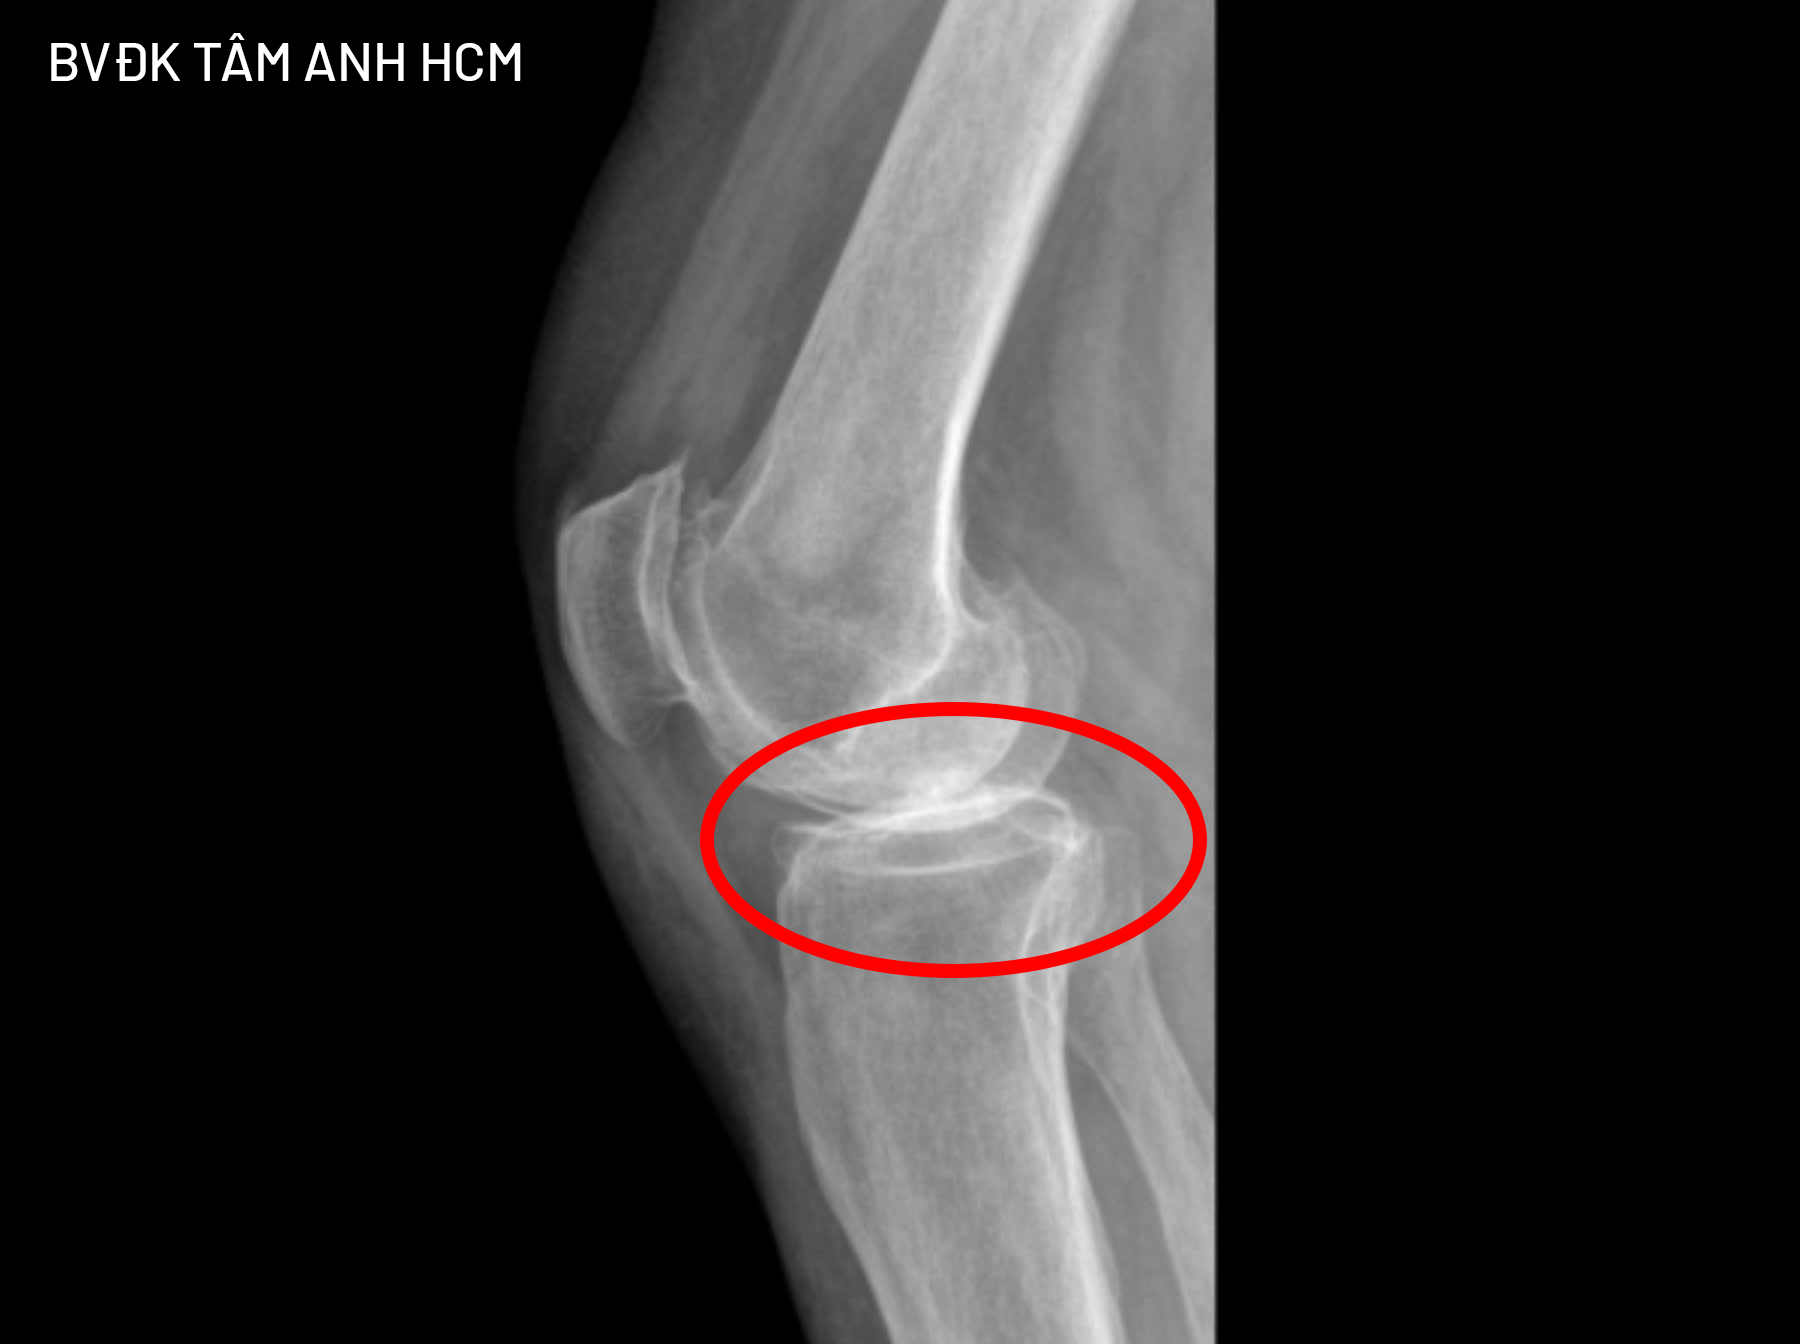

X-ray image showing Victoria's knee cartilage almost completely gone, with bone ends rubbing against each other. *Photo: Provided by the hospital* |

Although doctors in the US had not yet recommended surgery, Victoria, experiencing intense pain, was referred by an acquaintance to Tam Anh General Hospital in Ho Chi Minh City, Vietnam, for treatment. Dr. Dang Khoa Hoc, Head of the General Orthopedic Trauma Department, diagnosed Victoria with stage 4 chronic knee osteoarthritis, the most severe stage of the disease. Her joint cartilage was almost completely gone, with bone ends directly rubbing against each other, and inflammatory fluid from the degeneration caused pain and joint stiffness.